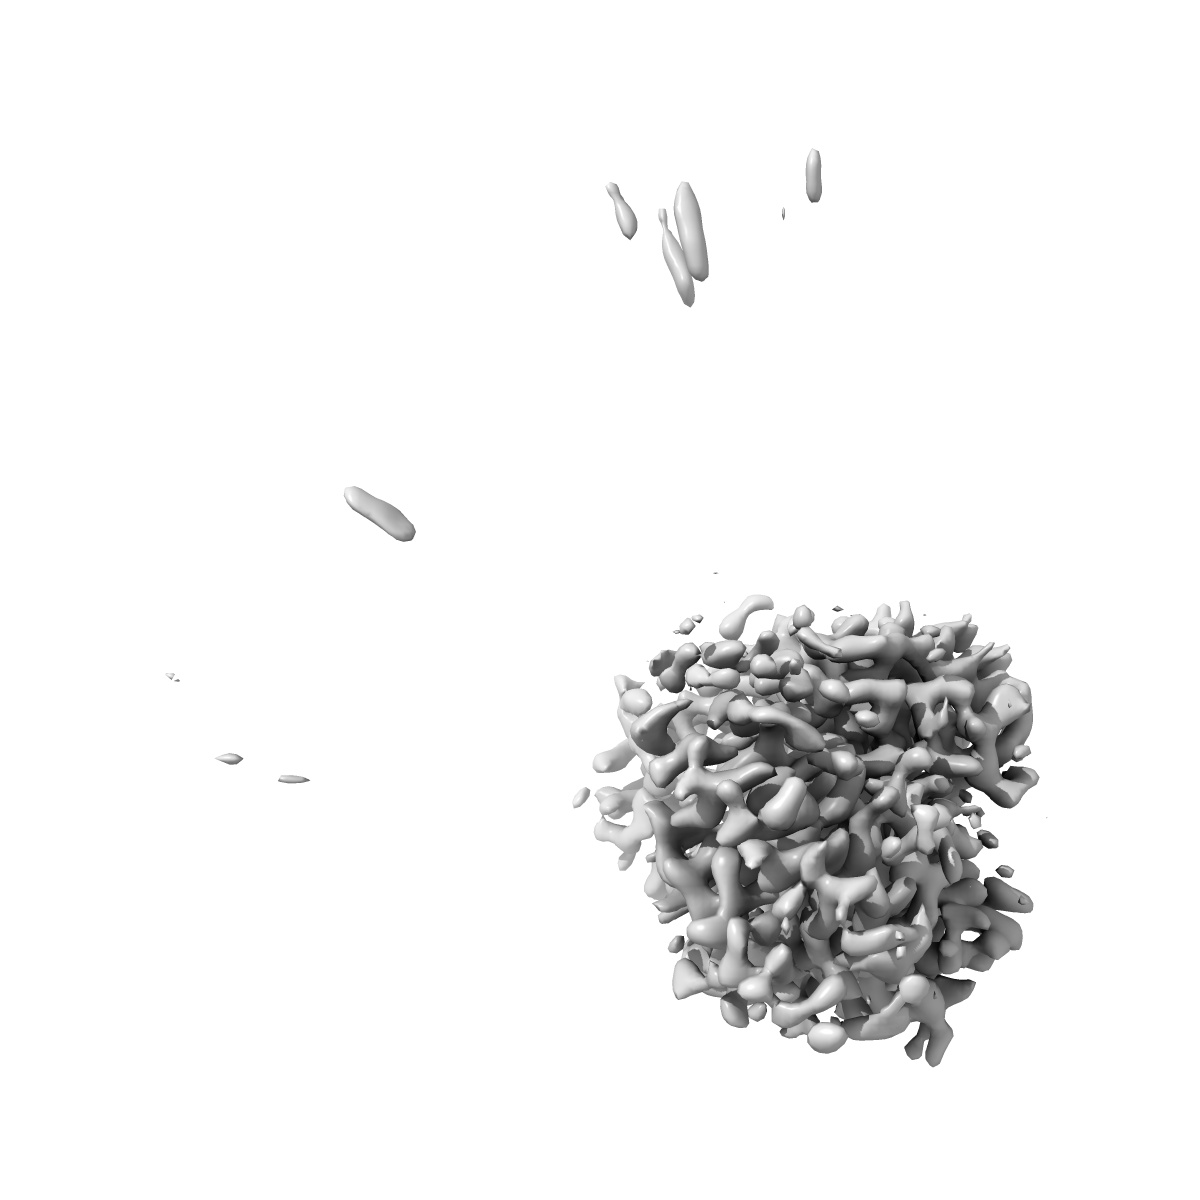

Cryo-EM structure of human monoclonal antibody C74 targeting IT4VAR22 CIDRa1.7

Single-particle3.35 Å

Sample: Plasmodium falciparum Erythrocyte Membrane Protein 1 in complex with human monoclonal antibody

Fitted models: 8vdg

Broadly inhibitory antibodies to severe malaria virulence proteins.